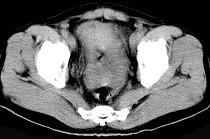

问题 58岁,间断腹部隐痛9个月,贫血3个月,近日加重并伴有柏油样便,CT所见如图,最可能诊断是()

选项 A.小肠淋巴瘤 B.小肠恶性间质瘤 C.小肠重复畸形 D.小肠癌 E.小肠淋巴肉瘤

答案 E